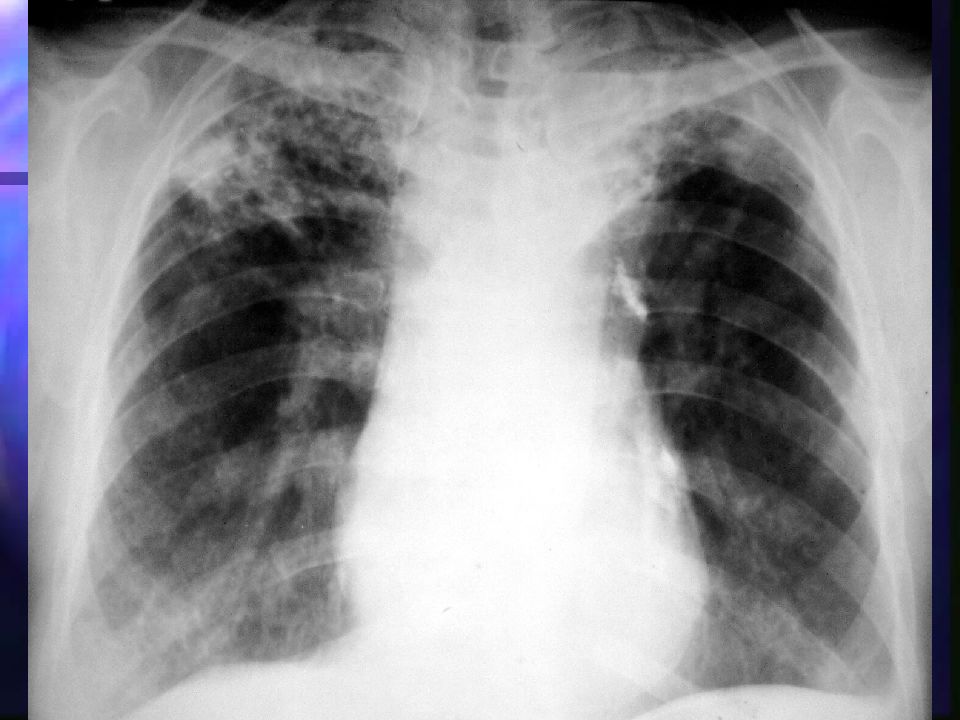

Рентгенологические изображения и синдромы патологии легких

Раздел: Кадры-подсказки